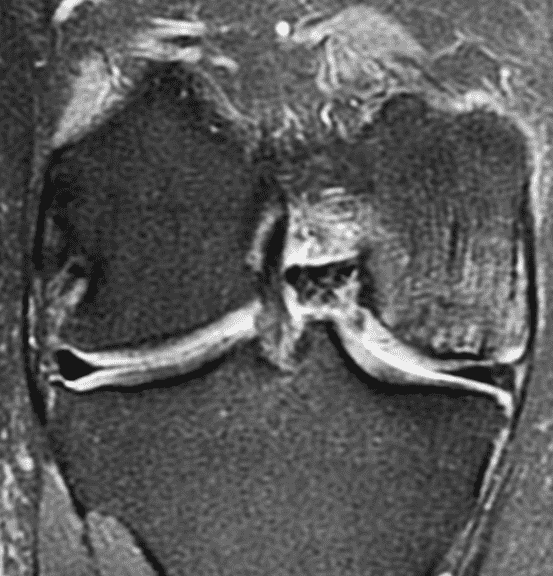

A 32-year-old man suffered a traumatic chondral injury to the medial femoral condyle that was treated with an osteochondral allograft 20 months previously. Representative images from a current knee MRI include (1A) coronal fat-suppressed fluid-sensitive and sagittal (1B) T1-weighted, (1C) proton density-weighted, and (1D) T2-weighted sequences. Are the post-operative MRI findings normal and expected, or abnormal and pathologic? Based on these images, would you characterize the procedure as a success or failure?

Figure 2: (2A) On the coronal image, the margins of the osteochondral graft are faintly visible (arrowheads). Both the graft and underlying bone show mild marrow edema, an expected finding. (2B) The T1-weighted image shows continuity of the marrow in the graft (asterisks) with the underlying bone, indicating osseous integration. A bioabsorbable pin (arrow) used for graft fixation is partly visible. (2C) The proton density-weighted image shows a low signal intensity seam (black arrow) between the native cartilage and transplant, as well as a defect in the subchondral bone plate of the graft (red arrow) where the pin was drilled, both normal findings. (2D) The T2-weighted image shows a smooth, congruent articular surface (arrows), restoring the normal anatomy, and a tiny subchondral cyst. No findings are present to suggest graft failure. The patient’s current symptoms were attributed to pathology elsewhere in the joint (not shown).

Successful osteochondral allograft procedure.

The postoperative imaging appearance of osteochondral allografts is similar to autografts (Figure 2).33 The subchondral bone plate of the donor and recipient sites do not have to match, but the articular surface should be congruent. Grafts that fail to incorporate by one year have a poor prognosis. Persistent marrow edema (beyond 12 months), a thick graft interface containing cysts or fluid, and subsidence of the graft are associated with poor osseous healing and worse outcomes. Extensive host marrow edema and severe synovitis may be a clue to immunologic rejection of the graft (Figure 18).21, 34